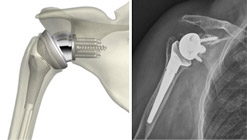

Protesi inversa: in questo tipo di protesi le componenti articolari sono invertite. L’emisfera viene impiantata nella glenoide mentre la porzione concava con cui si articola viene inserita nell’omero. Questa protesi così particolare è indicata nei pazienti con una rottura completa dei tendini della cuffia dei rotatori che quindi avrebbero un risultato funzionale dopo impianto di una protesi convenzionale non brillante. Il concetto della protesi di rivestimento è l’utilizzo del deltoide come motore della spalla in alternativa alla muscolatura della cuffia non più funzionale.